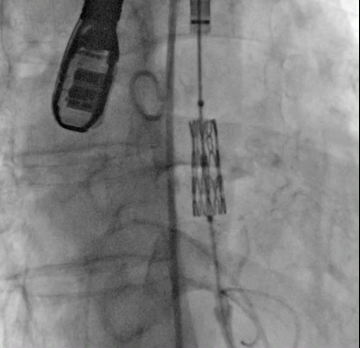

病例3(经颈动脉TAVI)

经术前详尽影像学重建、评估及病例讨论,最终决定在脑氧监测下对患者实施经左侧颈总动脉TAVI手术。术中左侧颈总动脉多次预扩后顺利置入血管鞘至升主动脉,跨瓣成功后先以23#球囊预扩,再“0位”植入25# Renatus介入主动脉瓣。手术耗时约2小时,介入主动脉瓣植入位置理想,功能表现良好,主动脉瓣峰值流速及平均跨瓣压差分别降至1.75m/s和5mmHg,造影及TEE观察仅有轻微瓣周漏,无中央型反流。术后左颈总动脉造影无明显狭窄,手术全程脑氧饱和度正常,无传导阻滞、无冠脉异常。

瓣膜“0位”释放 术后主动脉根部造影